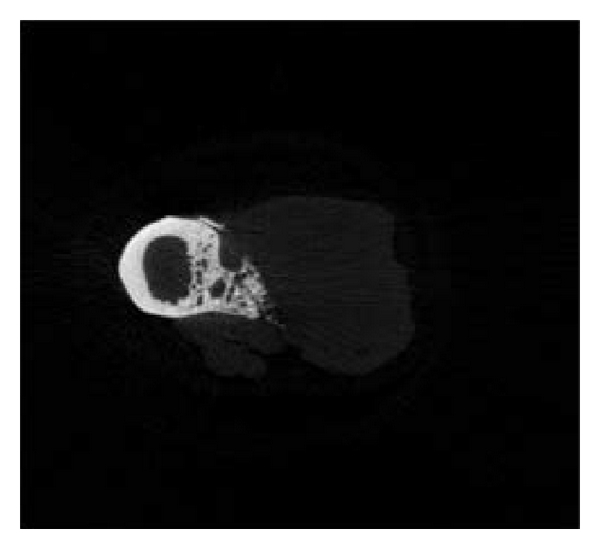

3.4. Micro-CT Examination

Micro-CT examination of 5 rabbits (2 from group A, 2 from group B, and 1 from group C) was conducted 3 months after surgery. The shapes of the rabbit bones at 3 months were shown in Figure 4. The bone defect in group A was not completely repaired, which in group B was completely repaired, while group C showed typical bone nonunion. The number of trabeculae per mm in groups A, B, and C was 0.40, 0.17, and 0.34, respectively. The bone mineral density in groups A, B, and C was 1.25434 mg/cc, 1.32521 mg/cc, and 1.3349 mg/cc, respectively, and the high bone density in group C resulted from osteosclerosis. The mass losses of PLLA and PLLA/PCL were 63.575% and 67.195%, respectively. These two scaffolds have fast initial degradation rate and then slowed down and cannot completely degrade 3 months after implantation.

(a)

(b)

(c)